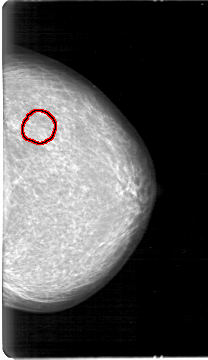

FILE: D_4026_1.LEFT_MLO.OVERLAY

TOTAL_ABNORMALITIES 1

ABNORMALITY 1

LESION_TYPE MASS SHAPE OVAL MARGINS OBSCURED

ASSESSMENT 0

SUBTLETY 3

PATHOLOGY BENIGN

TOTAL_OUTLINES 1

BOUNDARY

FILE: D_4026_1.LEFT_CC.OVERLAY